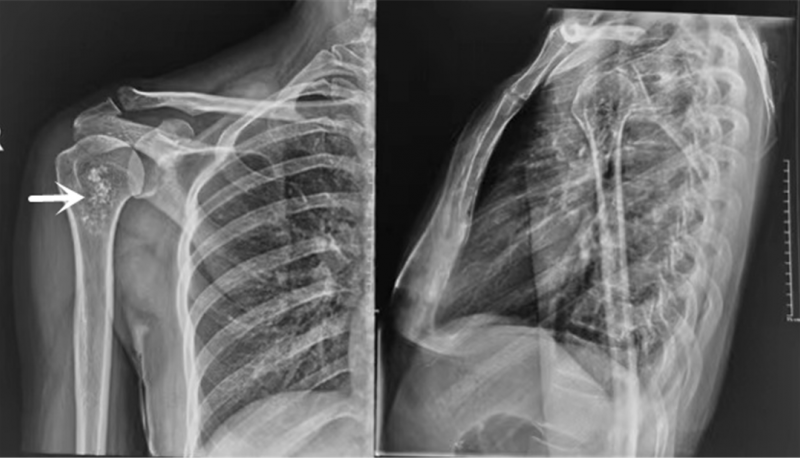

术前X线可见患者右肱骨近端骨病变。